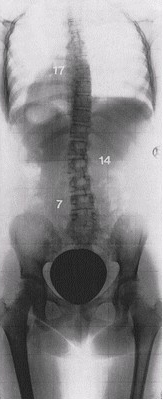

In 1989, 311 scoliosis patients 12 - 69 years old with an average Cobb angle of 50.5 degrees filled out pain questionnaires at the beginning and end of their treatment programs at the Katharina Schroth Klinik. They were asked to rate their pain on a scale of 0 - 5